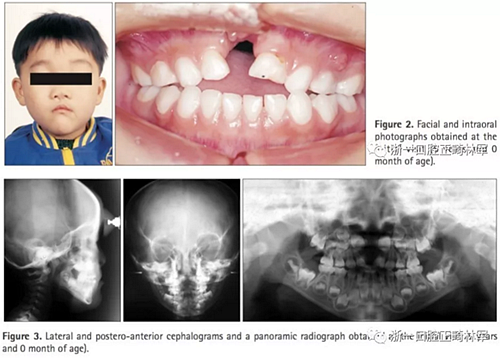

臨床檢查及診斷(圖2,3;表1):

患者表現(xiàn)為面中結(jié)構(gòu)過寬;口內(nèi)檢查提示前牙開合(覆合-2.5mm)及上牙弓窄縮。全景X線片顯示先天性缺失上頜乳中切牙及恒中切牙,前頜骨骨缺損和上頜左側(cè)乳切牙的萌發(fā)。頭側(cè)提示上下頜骨后縮(SNA,76.3°;SNB,74.8°;A to N,−3.9mm; Pog to N,−10.0mm) ,ANB角正常(1.5°),下頜平面角大(FMA,31.5°),下頜角大(125.4°)。上頜乳側(cè)切牙及下頜乳中切牙舌傾(primary U2 to SN,89.7°;primary IMPA,75.6°)。